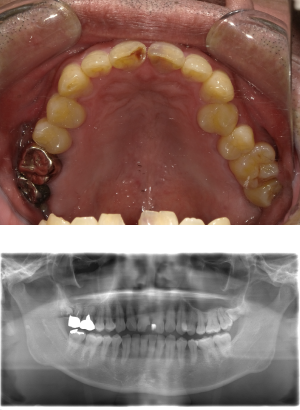

インプラント治療(左上5ソケット・GBR 右上2左上13GBR)

| 年代・性別 | 50代・男性 |

| 主訴 | 入れ歯だと咬めなくてつらい。 |

| 部位 | 上顎②1①2③4⑤Br |

| 治療期間 | 約9ヶ月 |

| 費用 | ¥1,794,100(税込) |

| 副作用・リスク |

|